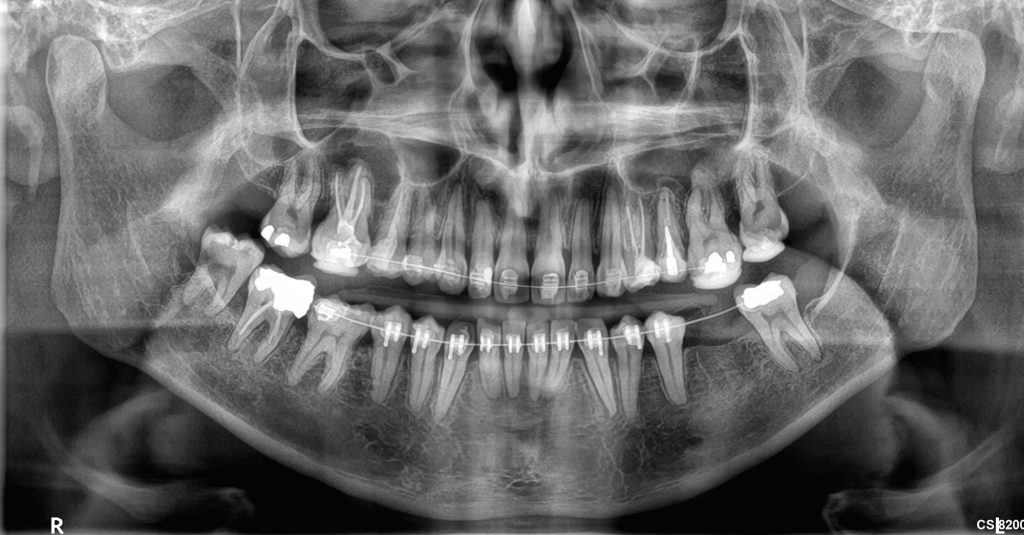

cs82003d-klinikes-eik-05 Published 14 February 2021 at 2000 × 1044 in cs82003d-klinikes-eik-05 ← Previous Next →